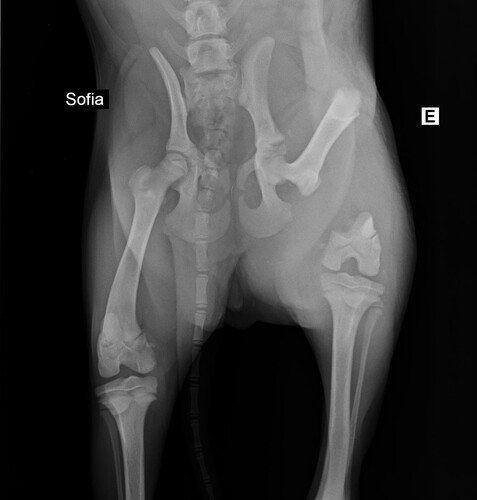

A primeira tia veterinária que me avaliou no dia 01/07, verificou através de exames de raio-x que eu estava com uma fratura muito feia na minha patinha traseira e disse que eu estava com muita dor. Ela falou que eu teria que ficar internada para tomar medicação e possivelmente realizar uma cirurgia na patinha. Além disso, com o resultado do exame de sangue, foi constatado que eu estava com anemia e alterações hepáticas.

No dia 03/07 tive uma consulta com o veterinário ortopedista e ele disse que aquele dodói não era uma fratura de atropelamento, e sim de ESPANCAMENTO. Ele também falou que eu precisaria fazer uma cirurgia para colocar implantes no ossinho da minha patinha e para a amputação da cabeça do fêmur. A tia que me resgatou perguntou ao ortopedista se eu ficaria com algum problema de mobilidade e ele disse que não devo ficar, mas que o ideal é eu fazer fisioterapia pós operatória.